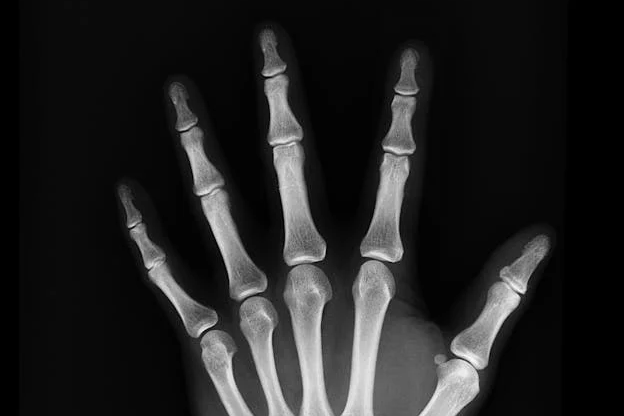

습관성 탈골이란?

습관성 탈골은 관절이 한 번 탈골된 이후, 반복적으로 같은 부위의 탈골이 발생하는 상태를 말합니다. 주로 어깨 관절에서 많이 발생하지만, 턱, 무릎, 손가락 등 다양한 관절에서도 나타날 수 있습니다. 처음 탈골이 생겼을 때 제대로 된 치료가 이루어지지 않으면 관절의 안정성이 떨어지면서 습관적으로 빠지는 현상이 나타나게 됩니다.